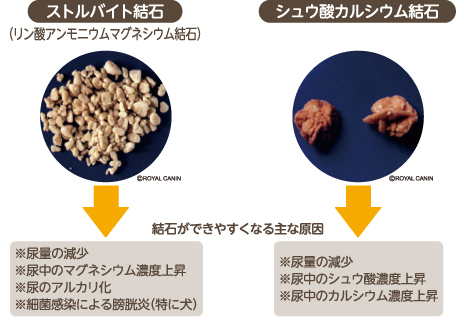

犬の尿路結石で多いのが「ストルバイト結石」です。 ストルバイト結石とは、どのようなことが原因で起こるのでしょう。 また、ドッグフードに気を付ける必要があるとされていますが、どのような内容が良いのか知りたいですよね。 そこでこの記事では、犬のストルバイト結石の原因や. 腹腔鏡を使った犬の膀胱結石摘出手術 こんにちは。 自由が丘動物医療センター院長の寺村です。 今回は、腹腔鏡手術のなかでも避妊手術に次いでよく行う 「膀胱結石摘出手術」 についてご紹介します! 膀胱結石摘出を腹腔鏡でする最大のメリットは. 犬、猫 尿石症〜腎・尿管・膀胱・尿道結石〜 – 代官山のHALU動物病院 今回は日頃よく遭遇する膀胱結石や尿道結石、あまり気がつかない腎・尿管結石などの尿石症についてご紹介します。 尿石症とは 尿の通り道である尿路系 (腎、尿管、膀胱、尿道.

8 犬の餌情報局 0528 フォローしました 人間にとっても、結石は激痛を伴う嫌な病気です。 犬の場合は、無症状で過ごしているケースもありますが、油断は禁物。 今回は、犬の結石の原因について勉強していくことにしましょう。 原因を知れば、飼い主さんとしてできる対策もできるので、愛犬をしっかりサポートしてあげてくださいね。 また 今は尿路. なぜ愛犬の膀胱炎は繰り返す?5つの原因 繰り返す原因1.膀胱に石ができている 膀胱に石ができることを膀胱結石といいます。 犬の膀胱結石の原因のほとんどは ・ストラバイト(リン酸アンモニウムマグネシウム) ・シュウ酸カルシウム のどちらかです。. わんちゃんの膀胱結石を手術治療しました 結石の種類や大きさなどにより治療方針が異なります 尿路結石は、おしっこの中に含まれるミネラルが何らかの原因によって塊となり、排泄されなくなってしまうことで起こります 膀胱でできた塊を膀胱結石といい、尿道でできた塊のことを尿道結石といいます 結石の種類はいくつかあります 1.リン酸アンモニウム.

犬の膀胱結石とは、尿をためる袋とも言うべき膀胱に結石を生じた状態を言います。 膀胱 (ぼうこう)とは腎臓から送られてくる尿を一時的に溜める袋状の器官であり、左右の腎臓から尿管を通して尿を受け取り、尿道を通して体外に排出します。 膀胱結石は尿路結石の中で最も発症頻度が高く、多くは 膀胱炎 に引き続いて起こります。 尿道が短くて細菌の進入. うえの犬猫病院は犬 リンク 採用情報 お問合せ 症例紹介 膀胱結石 膀胱結石とは 膀胱結石は膀胱炎や細菌感染、尿路閉塞の原因になります。特に尿路閉塞が危険で、結石が排尿路に詰まると急性腎不. Case42 膀胱結石の犬の1例 血尿と頻尿を主訴に来院した8歳の雄のワンちゃんです。 4ヶ月前にも同様の症状がありましたが抗生剤の投与で改善しました。 今回も同様の治療を試みましたが間欠的に血尿が続き、再発ということもありレントゲンと超音波検査を実施しました。 レントゲン検査では膀胱領域に数ミリの結石を認め、超音波検査でも複数の結石が確認され.